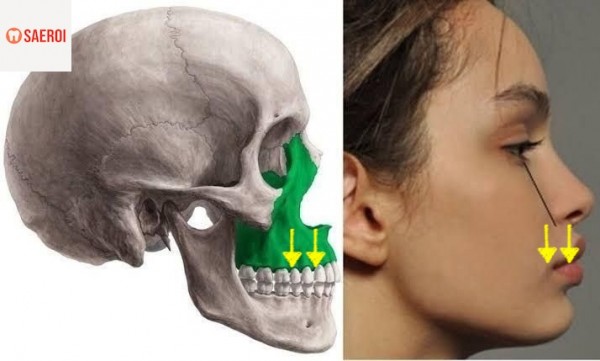

(4) 잇몸뼈(위턱뼈)의 수직적 성장

성장기에 얼굴의 위턱뼈와 아래턱뼈는

아래로 그리고 앞쪽(전방)으로 성장을 하게 되는데

이때 아래쪽 방향으로의 성장이 과하게 되면

수직적으로 긴 얼굴 모습을 가지게 되고

잇몸의 길이도 길어지게 되어

거미스마일 경향을 가지게 됩니다.

(4) 양악수술(악교정수술)

위턱뼈와 잇몸뼈의 수직적 성장이 과도하여

그 정도가 심한 경우에는

어쩔 수 없이 외과적인 수술이 필요한 경우도 존재합니다.

과도하게 자란 위턱뼈(빨간색 부분)를 절제하고

남은 부분은 이어주어

뼈의 길이를 짧게 만들어 주는 방법입니다.

외과적인 수술로 진행되다 보니

그 효과가 매우 드라마틱 합니다.